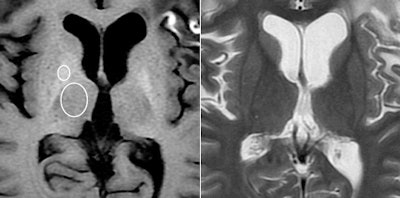

MRI of a 45-year-old woman with glioblastoma treated with surgery, chemotherapy, and radiation therapy. Unenhanced T1-weighted image (above, left) shows high-signal-intensity globus pallidus. Fast spin-echo T2-weighted image (above, right) at same level. Unenhanced T1-weighted image (below, left) shows high-signal-intensity dentate nucleus. Fast spin-echo T2-weighted image (below, right) at same level. Images courtesy of Radiology.

The analysis showed a significant correlation between the number of previous contrast administrations and signal intensity in the dentate nucleus and the globus pallidus, according to the researchers. Hyperintensity was significantly greater in patients who had received contrast, compared with those who received unenhanced scans.

Increased signal intensity in the dentate nucleus and globus pallidus on unenhanced MRI may be due to the number of previous gadolinium-based contrast administrations, Kanda and colleagues noted.